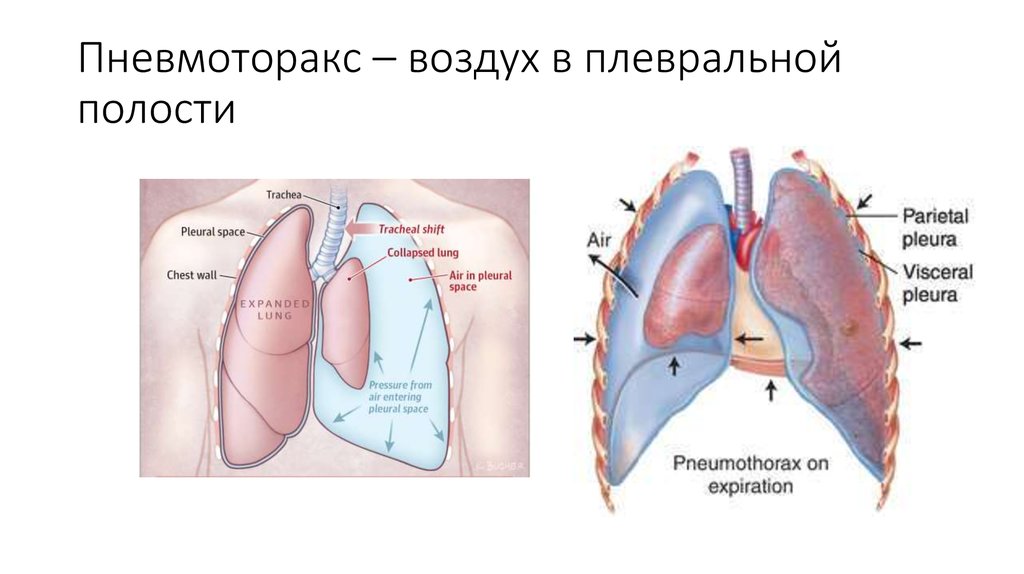

Схемы дыхания: Пневмоторакс на изображениях